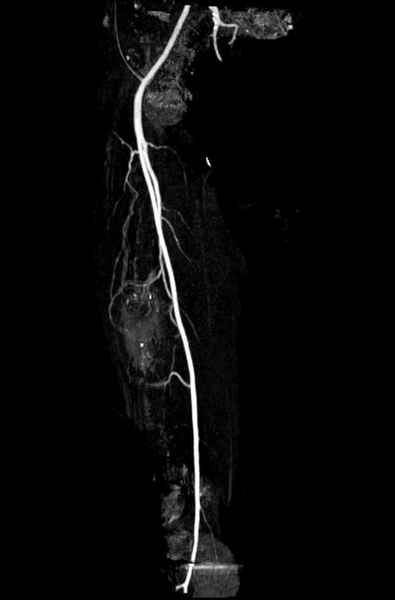

Для предупреждения кровотечения во время рассверливания, за день до операции провели эмболизацию сосудов питающий метастаз. http://radiology.rsnajnls.org/cgi/reprint/150/3/673.pdf (7-11, 12-15-16)

Имя     : 7 angiogramm 3.jpg

Тип     : image/jpeg

Размер  : 22792 байтов

Описание: отсутствует

Url     : http://weborto.net:8080/pipermail/ortho/attachments/20090331/478d25c4/attachment-0017.jpg